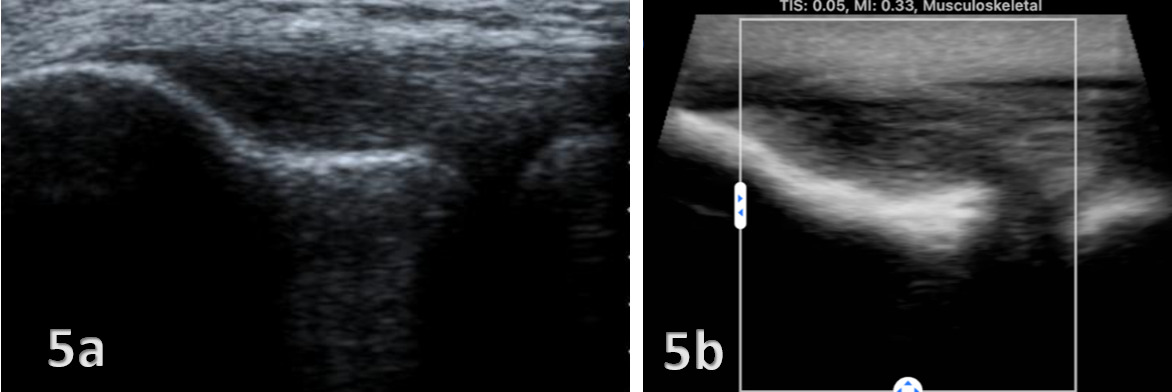

Figures 4 and 5 demonstrate lateral elbow pathologies.